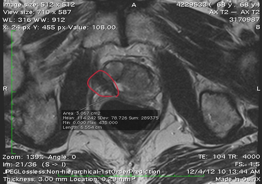

Treatment: Focal HIFU

5 years after Focal HIFU, the patient is cancer free as determined by Artemis MRI-guided fusion biopsy. The area in red represents scar tissue completely replacing the tumor.

This man has a completely normal sexual and urinary function.